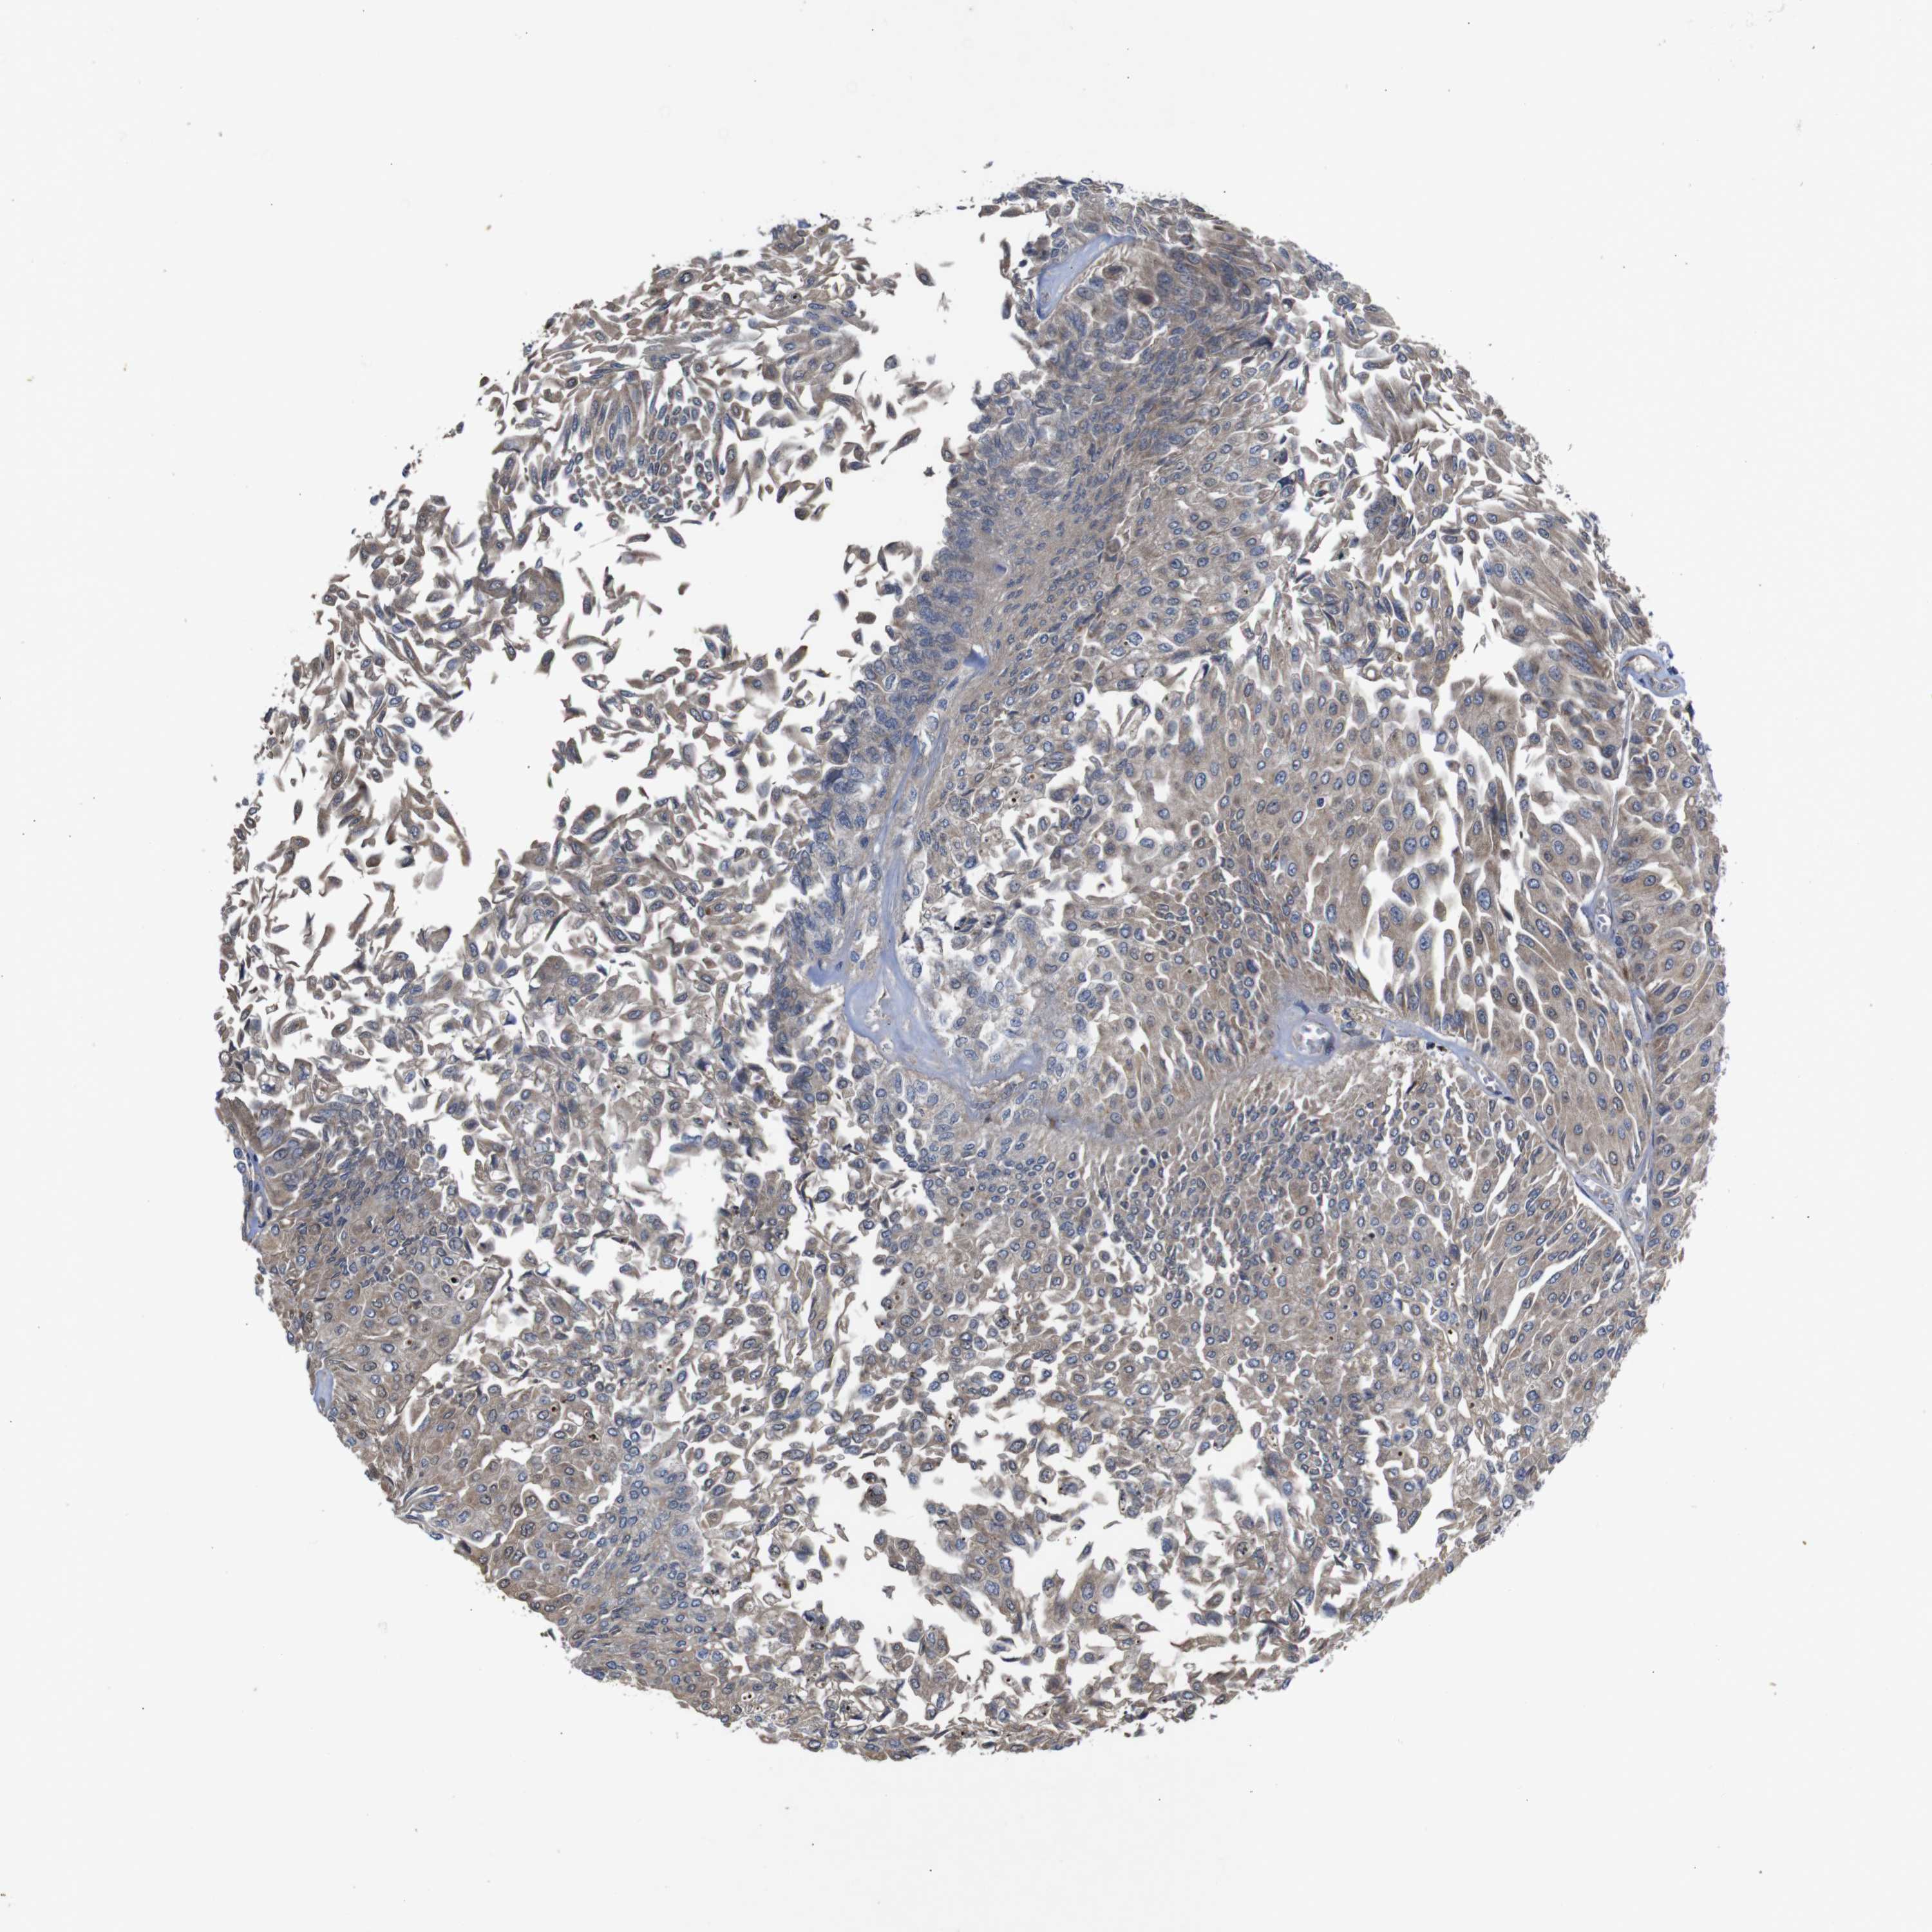

UROTHELIAL CANCER - Protein expressioni

A mouse-over function shows sample information and annotation data. Click on an image to view it in a full screen mode. Samples can be filtered based on level of antibody staining by selecting one or several of the following categories: high, medium, low and not detected. The assay and annotation is described here.

Note that samples used for immunohistochemistry by the Human Protein Atlas do not correspond to samples in the TCGA dataset.

Antibody stainingi

Antibody staining in the annotated cell types in the current human tissue is reported as not detected, low, medium, or high, based on conventional immunohistochemistry profiling in selected tissues. This score is based on the combination of the staining intensity and fraction of stained cells.

Each image is clickable and will lead to virtual microscopy that enables deeper exploration of all samples and also displays staining intensity scores, fraction scores and subcellular localization as well as patient and tissue information for each sample.

Antibody HPA012542

Antibody CAB009329

Antibody CAB015217

Staining

High

Medium

Low

Not detected

Intensity

Strong

Moderate

Weak

Negative

Quantity

>75%

75%-25%

<25%

None

Location

Nuclear

Cytoplasmic/membranous

Cytoplasmic/membranous,nuclear

Urothelial carcinoma, Low grade

Urothelial carcinoma, High grade